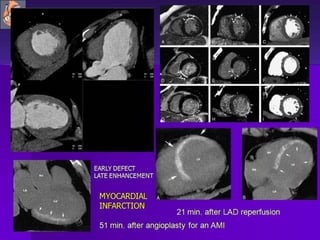

Coronary Angiography